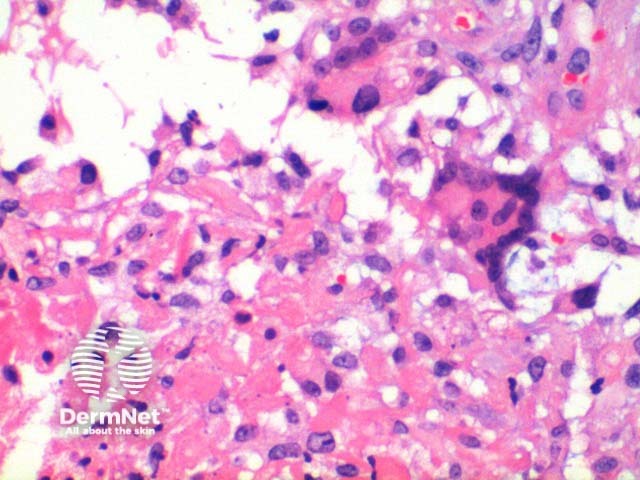

At low power the histological pattern seen in pilomatricoma is of a well-circumscribed nodulocystic tumour (Figure 2). While predominantly seen within the lower dermis, extension into the subcutaneous tissue is not uncommon. The tumour is comprised of a basaloid proliferation resembling the hair matrix cells, which matures into structureless eosinophilic cells lacking nuclei called shadow cells (Figures 3 and 4). The shadow cell area represents differentiation towards the hair cortex. Frequently there are areas of calcification within the shadow cell regions (Figure 5). A histiocytic infiltrate with multinucleated cells forms at sites of rupture (Figure 6).

Figure 6